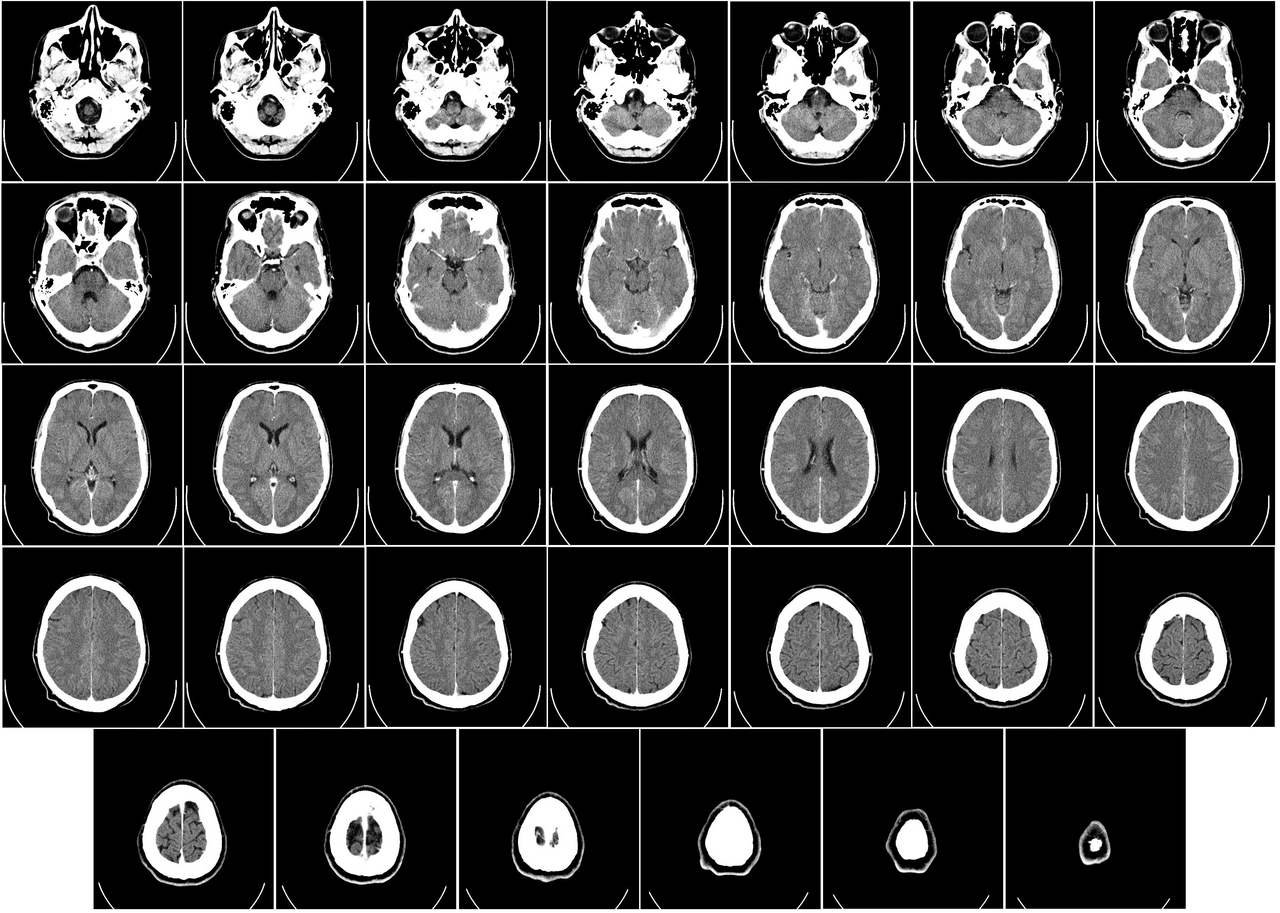

Dr. Gottfried Schlaug sat in a University of Heidelberg laboratory in 2004, staring at scans that fundamentally altered our understanding of the human skull. These images revealed more than abstract emotion or fleeting thought.

They displayed dense, physical matter that looked starkly different from the brains of people who never touched a massive orchestral percussion kit or a Stradivari and a bow. The scans showed that musicians possessed larger volumes of gray matter in the left auditory cortex and the posterior intural parietal sulcus. This density occurs because the brain adapts to the relentless, heavy demands of auditory processing. The brain performs a literal, physical reconfiguration of its biological hardware.

Music functions as a structural demand on the human nervous system rather than a mere emotional experience. When we discuss musical brain plasticity, we describe the literal reshaping of neurons. The brain does not simply listen to a melody; it builds more roads to process it. Every repetitive scale, every grueling practice session, and every difficult rhythm leaves a physical footprint on the cortex. This process represents a biological transformation of the brain's architecture, not a metaphor for learning.

Gray matter handles the heavy lifting of our cognitive existence. This tissue contains the cell bodies of neurons and manages the processing of all sensory input. Musicians undergo a process where their brains expand specific regions to handle the complex input of pitch, timbre, and rhythm. This expansion happens because the brain optimizes itself for the specific tasks it performs most often. The brain operates as a machine that retools itself based on the input it receives.

Computed tomography of human brain - large.png

Credit: Wikimedia Commons